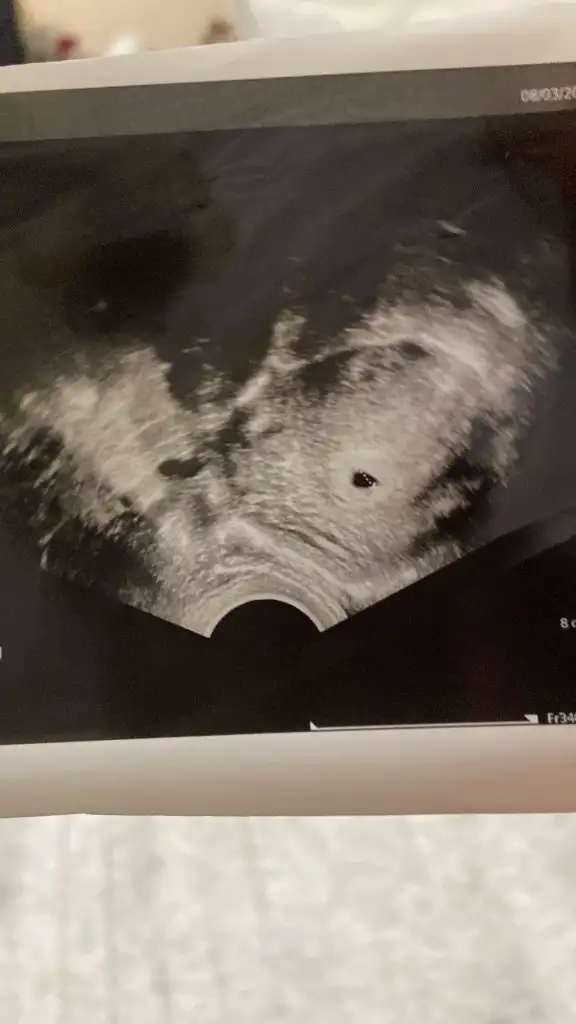

Merhaba erkek gibi görüyorum konumu açısından.Allah kucağınıza almayı nasip etsin inşallahMrb banada bakarmisin karından ulturoson. 6+7 haftalık

Bizim biraz küçük 5 hafta bize de söyleyin bari biraz riskli benim ki ama teselli olur inş bakalımYüzlerce ultrason görseli görmüş olabilirim sanırım edindiğim tecrubelerden, kesenin şekli ve bulunduğu konumuna bakarak az çok tahminde bulunabiliyorum naçizane:) kızımın ultrasonlari da benzerdi genelde kız oluyor bu konumda ama tabi net drunuz paylaşır